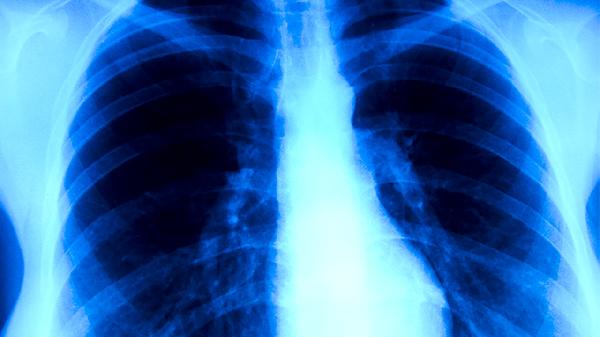

肺結(jié)核患者的飲食事項(xiàng)有哪些

肺結(jié)核患者需注重高蛋白、高熱量、高維生素飲食,可適量食用雞蛋、牛奶、瘦肉、魚類及新鮮蔬菜水果,避免辛辣刺激、油膩食物。